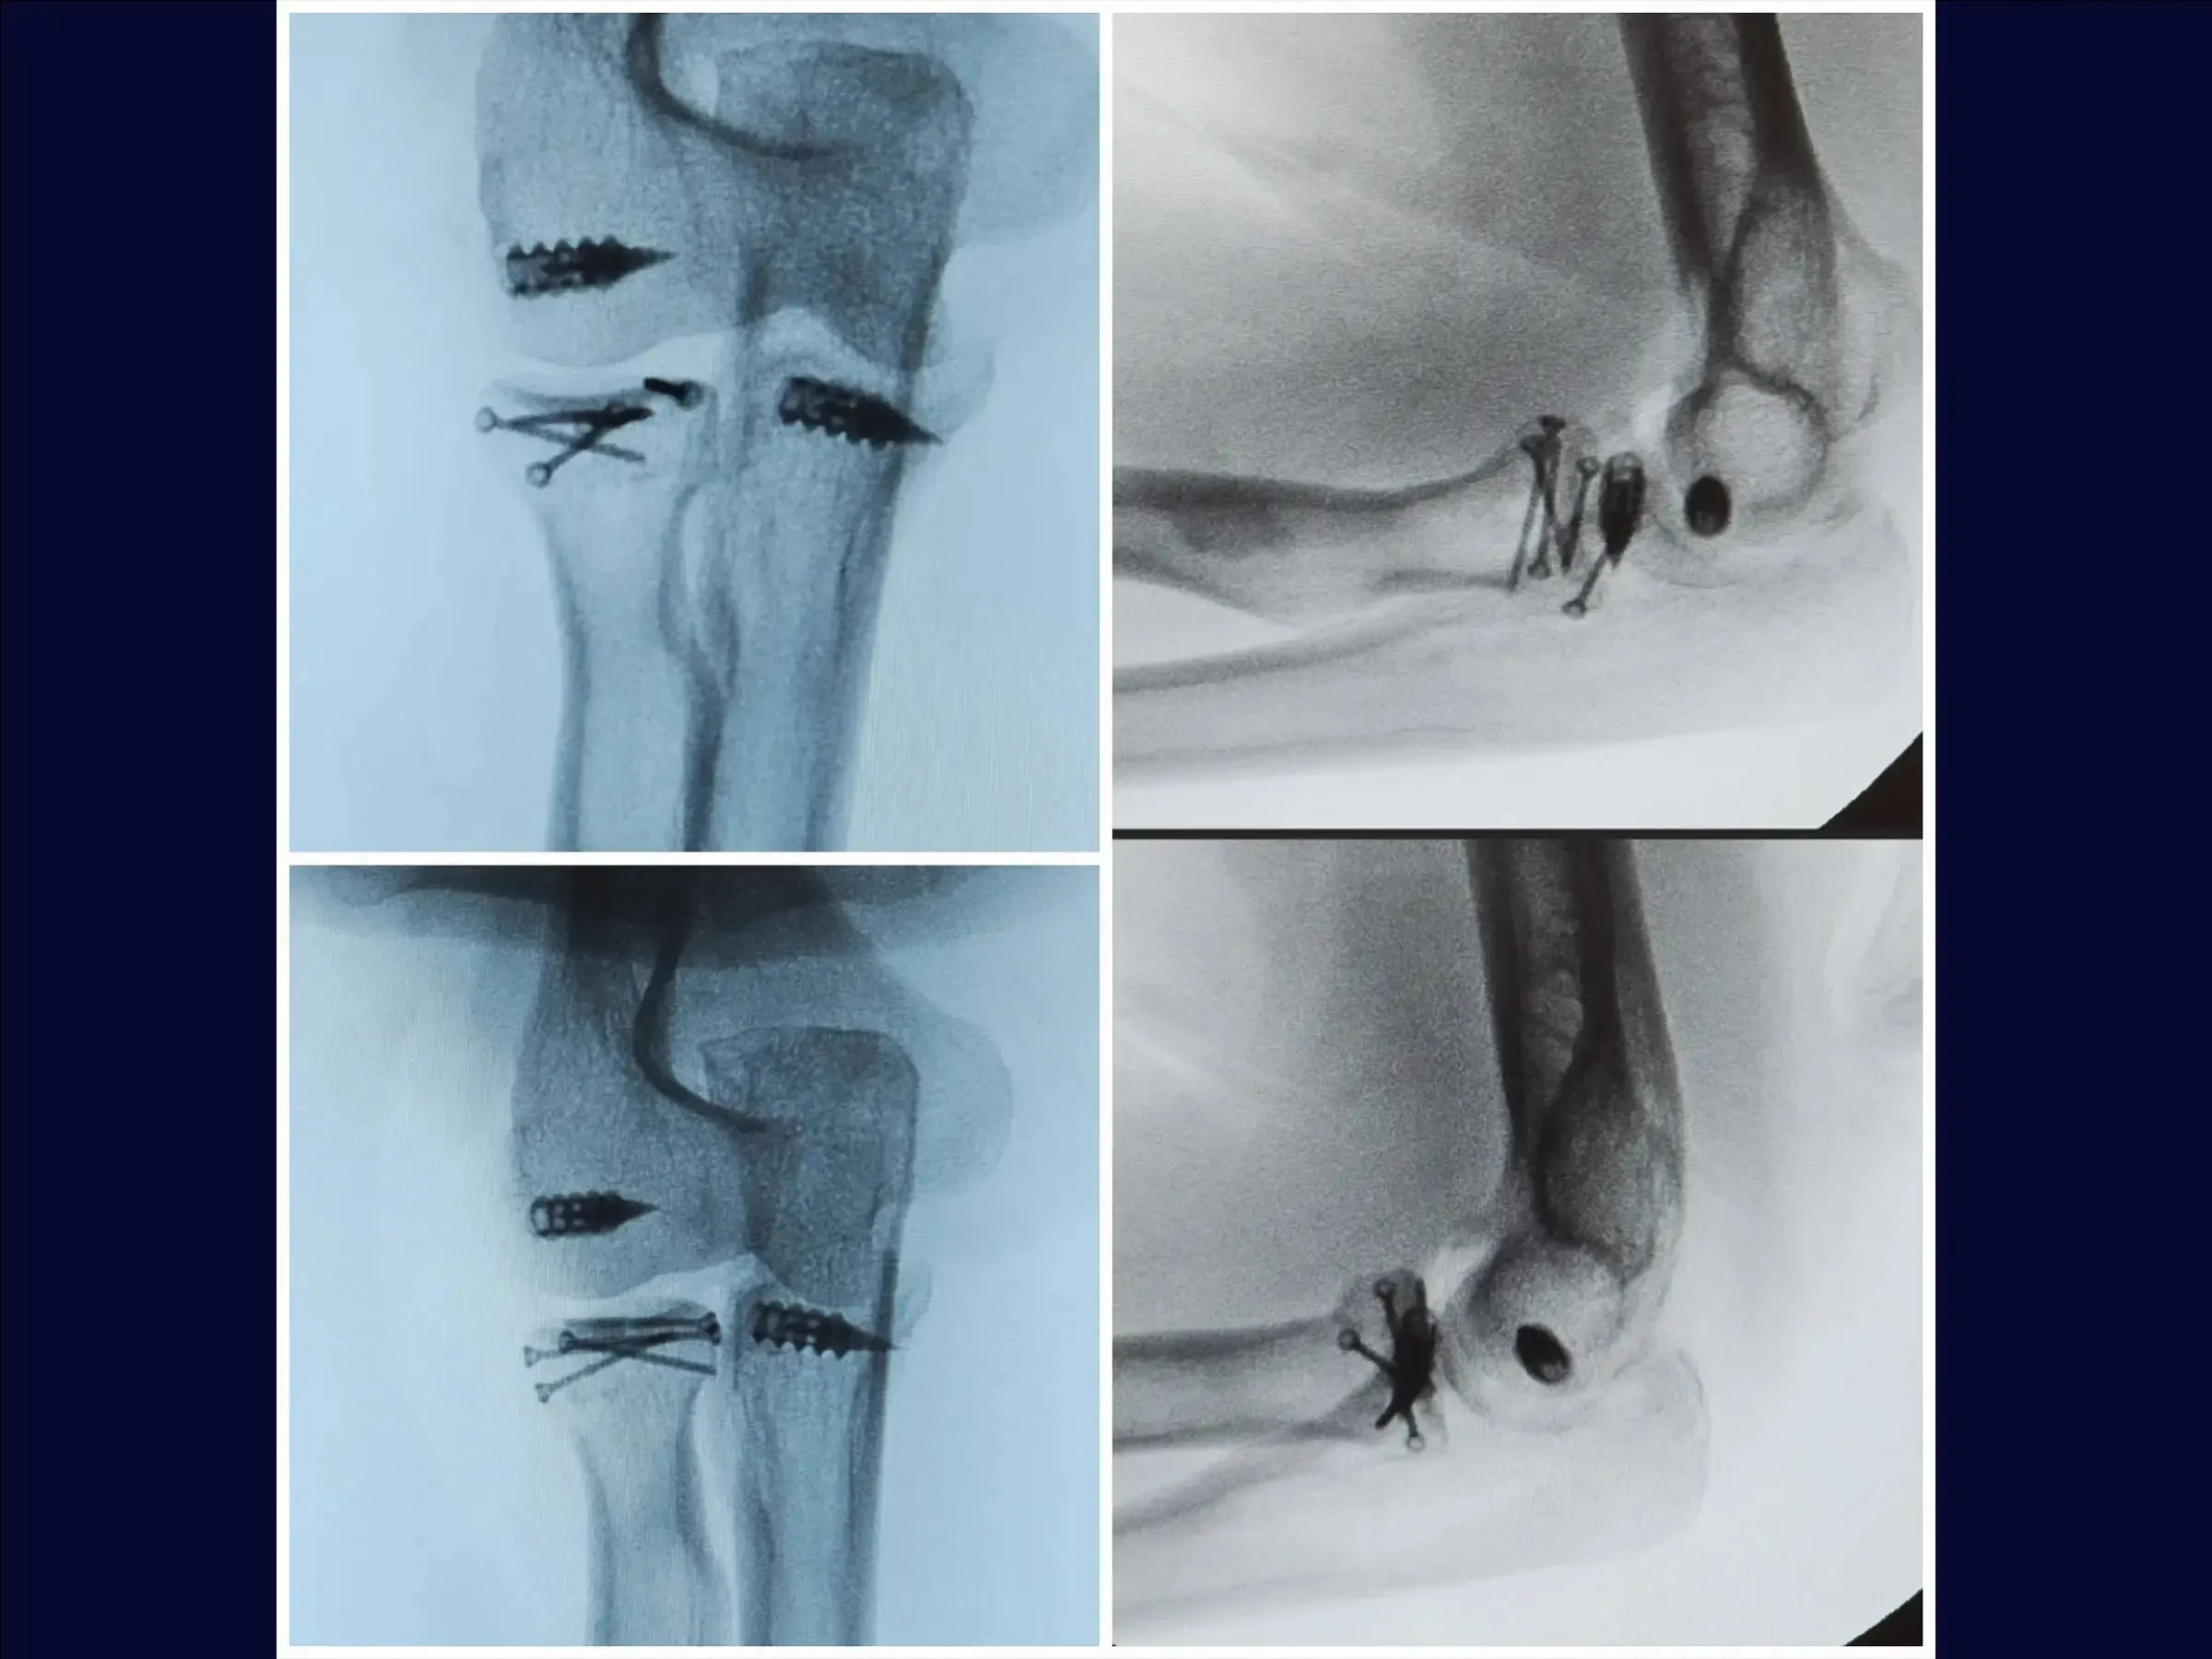

- Síntesis de cabeza radial Osteoss : utilizar tornillos de 1,5 mm, paralelos o divergentes, sin cruzar, para una fijación subcondral estable .

- Reparación del proceso coronoideo y la cápsula: utilice un ancla de metal de 5,0 mm y suturas de alta resistencia para suturar firmemente la cápsula articular anterior.

- Reparación del ligamento lateral: reinsertar el ligamento con ancla y ajustar con valgo para asegurar una tensión adecuada.

- Cierre y Prueba: Cerrar por planos y verificar el rango de movimiento intraoperatorio , asegurando la ausencia de bloqueos.